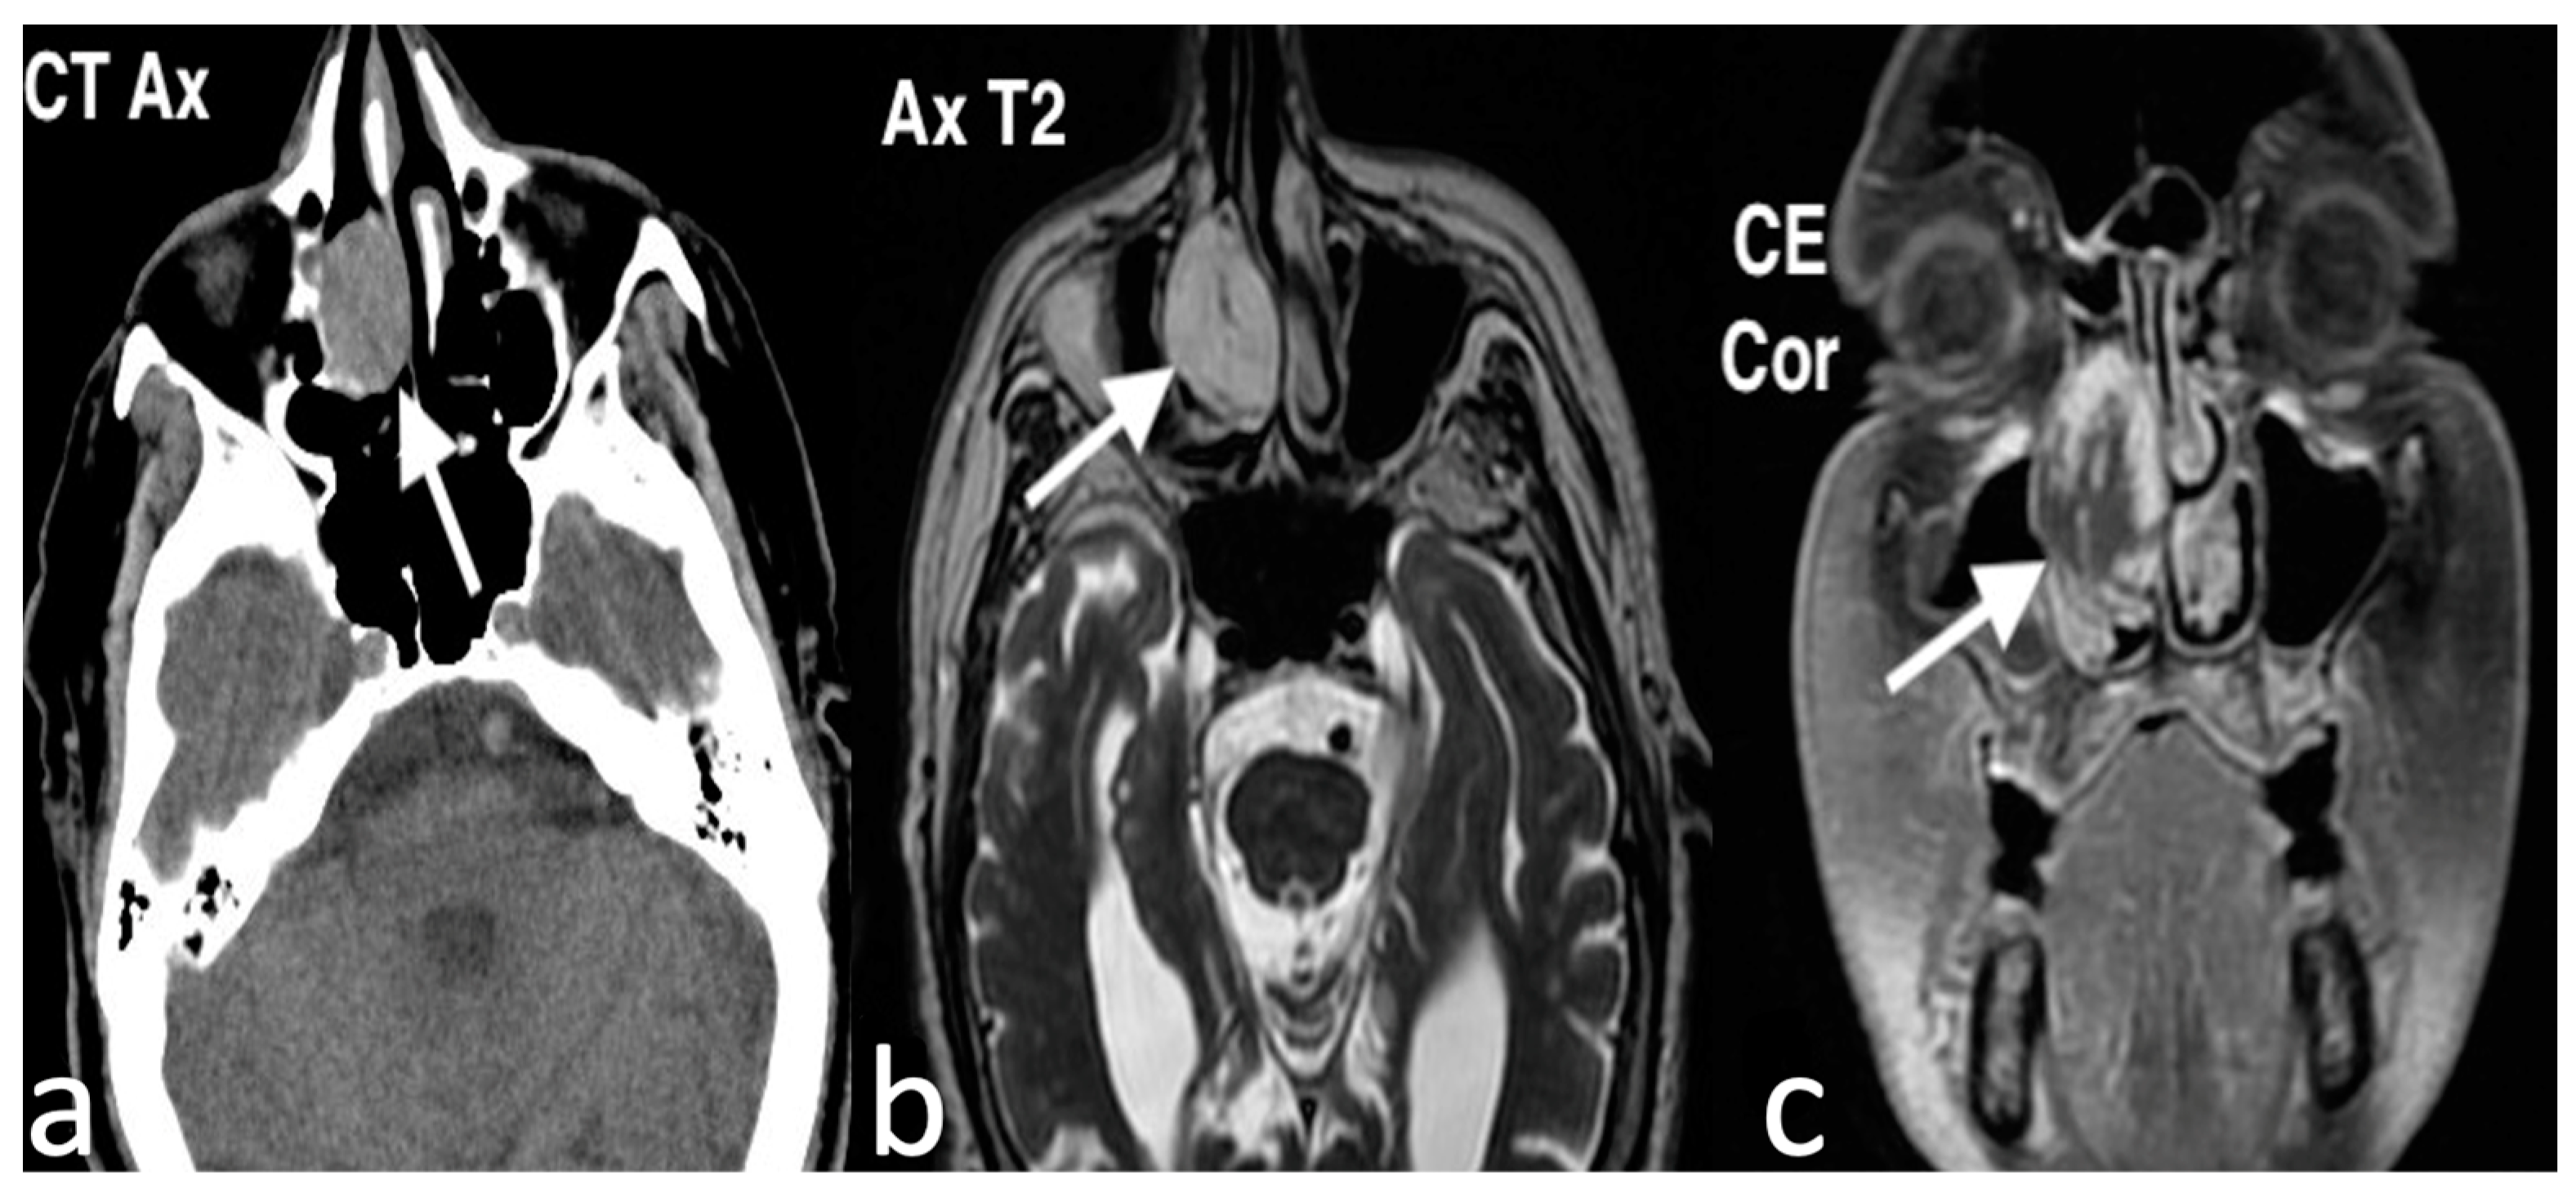

3.2.1. Lobular Capillary Hemangioma

3.2.2. Chondromesenchymal Hamartoma

3.2.3. Ossifying Fibroma